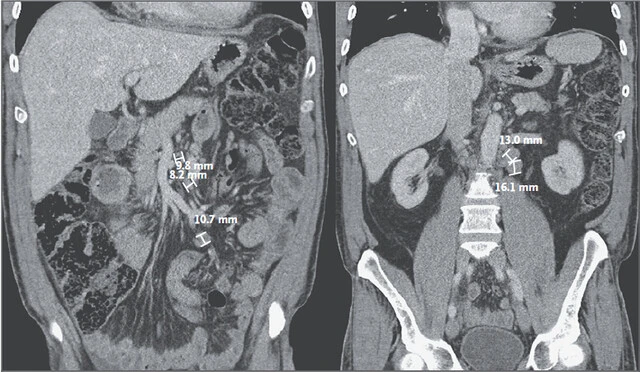

胸部 CT 显示轻度肺间质炎症,双侧胸腔积液。主肺动脉增宽,直径达 30.9 mm。小量心包积液。可见多个腹部巨大淋巴结,在扩张的近端空肠附近,见图 1 。

图 1:冠状面可见增大的,肠系膜旁边的淋巴结,图中已经测量出其具体大小。

CT 上看起来特别像淋巴细胞增生性疾病,或者涉及到空肠的癌症。淋巴结病会随着感染扩散,包括结核,结核菌素实验阴性并不能说明结核不存在,播散型肺结核本来实验就是阴性。只有外周淋巴活检之后才能确诊。